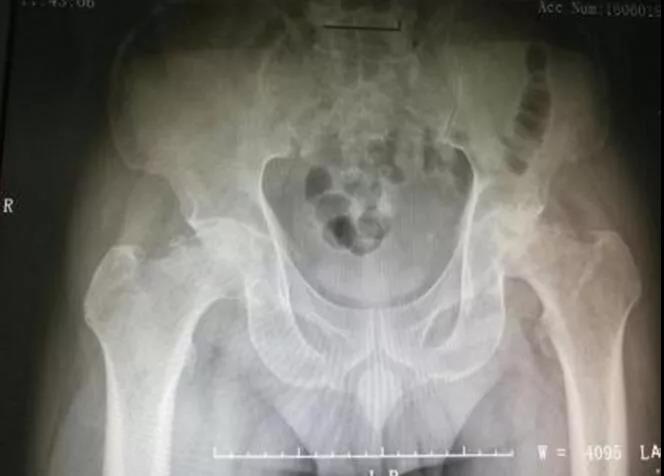

经过拍骨盆DR片后才发现病因所在:双侧股骨头缺血性坏死。通过当地医生介绍,遂转至五邑中医院骨五科住院治疗。

▲术前DR片